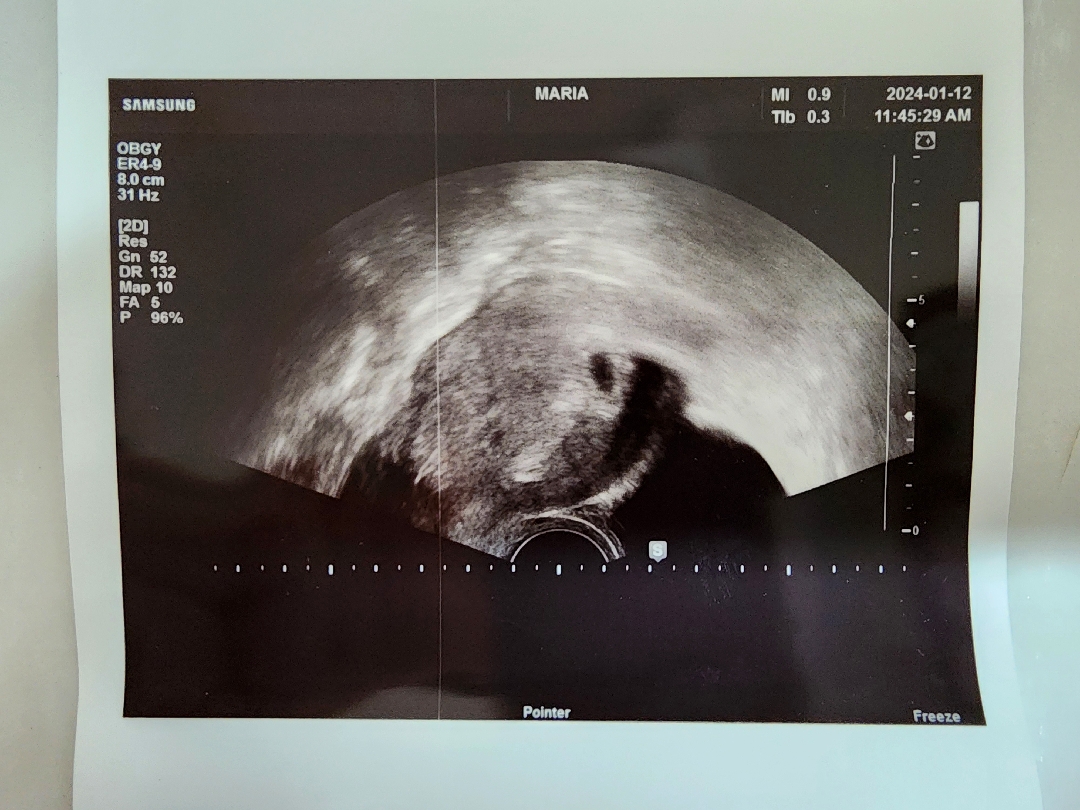

아기집 봤어요!

저번에 첫인사하며 걱정된다고 글 올렸는데, 병원 다녀왔어요ㅎㅎ 5주말 정도 된 것 같고 아기집이 잘 지어졌다구하네요ㅎㅎ 넘 신기해요! 제가 눈물이 많아서 보면 울 줄 알았는데, 그냥 우와..만했네요ㅋㅋ 아직 심장소리는 못들었는데 토요일에 가기로 했어요. 넘 기대돼요! 엄빠에게도 좀 이르지만 서프라이즈 임밍아웃했는데, 넘 좋아하시네요ㅎㅎ 그런데 베동님들도 가스가 많이 차시나요..? 변비가 아주 심하진않은데 매일 밤 가스가 넘 많이 차서 괴롭네요ㅜㅜㅋㅋㅋ 가슴팍 여드름도 나고 조금씩 유방통증도 있는데, 몸이 바뀌어 가는게 그저 신기하네요!